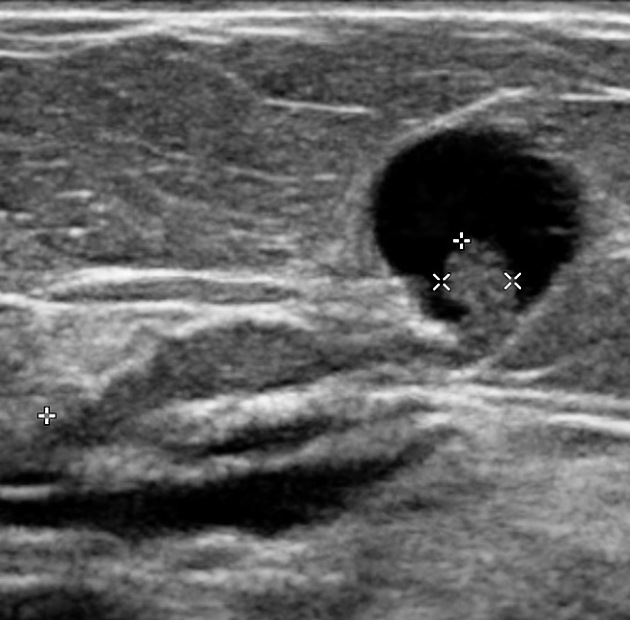

- Ultrasonography may be more sensitive than mammography for detecting IDP (L/C ST) and can reveal duct ectasia, nodules, or a cyst with or without a polyp.